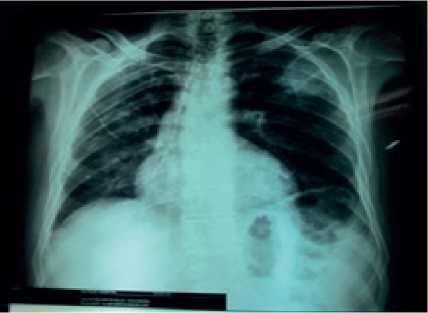

En la radiografía de tórax PA, tomada posterior al inicio de la terapia antimicótica, se evidencia desaparición de las opacidades con persistencia de algunas hiperclaridades y disminución importante del diámetro de la lesión principal en el lóbulo superior izquierdo (Figura 3).

Figura 3. Radiografía de tórax PA.Se evidencia desaparición de las opacidades con persistencia de algunas hiperclaridades y disminución importante del diámetro de la lesión principal en el lóbulo superior izquierdo.